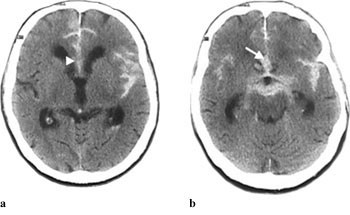

Subaraknoidalblødning ble påvist ved CT-undersøkelse hos 64 av 70 pasienter (91 %). Blod ble hyppigst påvist i basale cisterner (75 %), i fissura Sylvii (73 %) og i cerebrale kortikale sulci (67 %) (tab 1, fig 1 – 5). Funn forenlig med økt intrakranialt trykk (utvidet ventrikkelsystem, spesielt sideventriklenes temporalhorn og/eller overskyvning av midtlinjestrukturer, endret form av basale cisterner, utvisket overflaterelieff og/eller periventrikulært ødem) ble påvist hos 26 pasienter (41 %).

Opplysninger vedrørende cerebral angiografi forelå hos 64 av 70 pasienter med subaraknoidalblødning. Av disse hadde ti (16 %) normalt funn. Til sammen 63 aneurismer ble påvist hos 52 pasienter (81 %). Intracerebral arteriovenøs malformasjon ble påvist hos to pasienter. Hos seks pasienter ble det gjort samtidig funn av henholdsvis fire (n = 2), tre (n = 1) og to (n = 3) aneurismer ved samme undersøkelse. Aneurismer ble hyppigst påvist på a. cerebri media, a. communicans anterior og a. carotis interna (tab 2). Påvisning av blod i subaraknoidalrommet kunne gi indikasjon på lokalisering av aneurismet (tab 2, fig 2, fig 4). Prediksjon for påvisning av lokalisasjon av blødende aneurisme var kun meget god for aneurismer på a. cerebri media, hvor 12 av 13 aneurismer ble lokalisert korrekt. Det var dårligere prediksjon for aneurismer lokalisert til a. communicans anterior og a. carotis interna, med henholdsvis 11 av 18 og fire av ti aneurismer riktig lokalisert. Angiografi var utført hos åtte av ti pasienter med blod i septum pellucidum, og hos samtlige ble det påvist aneurisme på a. communicans anterior (fig 4). For de andre lokalisasjonene var det få observasjoner og lav treffsikkerhet.